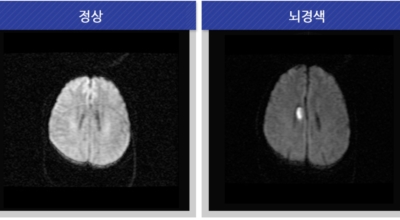

뇌조직은 평소에도 다량의 혈류를 공급받고 있는데 어떤 여러가지 원인으로 인해서 뇌혈관에 이루는 관이 막히는 경우 뇌에 공급되는 혈액량이 떨어지면서 뇌조직이 기능을 제대로 하지 못하게 되는데 이렇게 뇌혈류 감소가 일정 시간 이상 지속되다 보면 뇌조직의 괴사가 시작되어 회복 불가능한 상태가 되는데 이를 뇌경색이라 해요. 오늘 알아볼 질병은 뇌경색 초기증상이예요.

뇌경색의 경색이란 허혈성 괴사를 말해요. 여기서 허혈이란 혈관이 막히는 것을 말하고 괴사는 말 그대로 일부가 죽는 것을 말하는데 뇌경색의 경우 뇌의 혈관이 막혀 뇌세포 일부가 죽는 걸 의미해요. 뇌혈관이 막혔다 해서 혈액 공급이 안되는것은 또 아니에요.